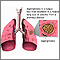

Although most people are often exposed to aspergillus, infections caused by the fungus rarely occur in people who have a normal immune system. The rare infections caused by aspergillus include pneumonia and fungus ball (aspergilloma).

There are several forms of aspergillosis: